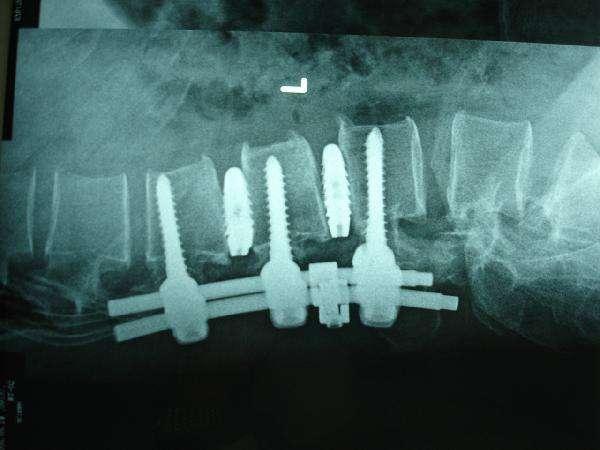

5.治療面では、腰部筋緊張は比較的治りやすく、理学療法、マッサージ、鍼灸、高周波などで治すことができるが、腰椎椎間板ヘルニアはより難しく複雑であり、通常は保存的治療、低侵襲治療などを行い、必要であれば手術も行う。

腰椎椎間板ヘルニア:初期の段階では、一般的な症状が明らかでない場合、保存的治療を行うことができる。病気が進行し、症状がより重くなり、保存的治療が無効な場合は、手術を考慮します。

- 一方、腰椎椎間板ヘルニアの保存的治療としては、手技療法、牽引療法、漢方燻蒸、薬用温湿布などの理学療法や漢方理学療法に加え、腰部や腹部の筋力を高める運動療法を行い、症状の緩和や病気の進行を抑制します。

- 腰椎椎間板ヘルニアの患者さんは、痛みが再燃すると動きが制限されることが多く、動きが不足すると腰椎や腰椎周囲の軟部組織の拘縮や萎縮を招き、病状をさらに悪化させる可能性があるため、必要に応じて薬物療法や毛髪の閉鎖によって痛みの症状を適時に緩和し、可動性を回復させることが大切です。

- また、病歴が長く、保存的治療で症状が緩和されない患者さんには手術が考慮されます。患者さんの状態によって、低侵襲手術と一般手術の選択肢が異なります。